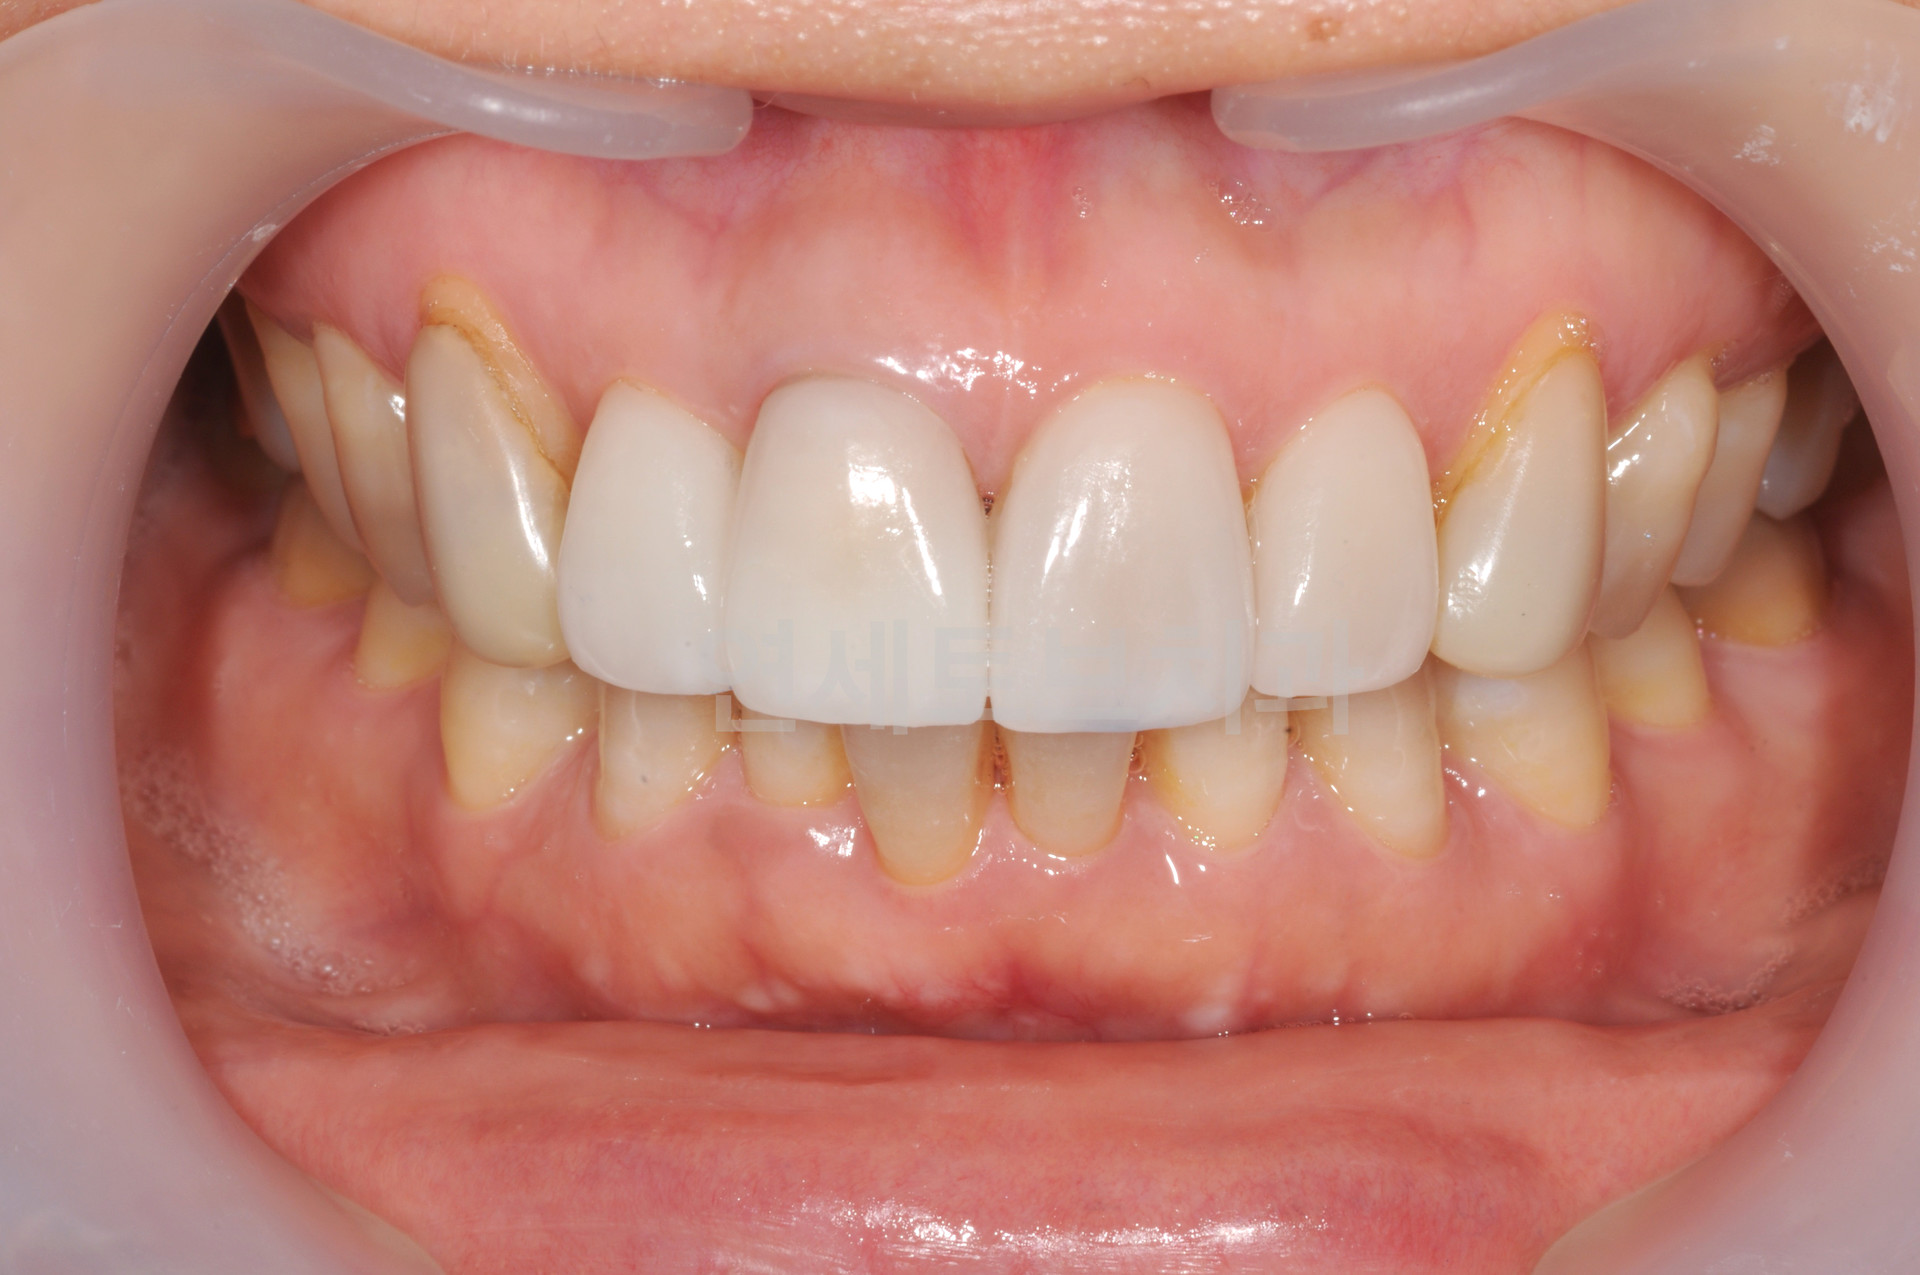

Before

올세라믹 크라운 시술 전

After

올세라믹 크라운 시술 후